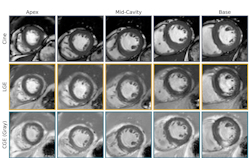

- Magnetization transfer imaging: This technique examines the magnetization exchange between macromolecules and water and provides a marker of overall tissue integrity, with newer approaches such as inhomogeneous magnetization transfer more specific to myelin lipids, she said.

- Diffusion Basis Spectrum Imaging (DBSI): This is a new diffusion tensor imaging approach that may provide more specific information about tissue microstructure and inflammation and edema, Laule said. DBSI findings in MS lesions suggest increased cellularity and inflammation markers, and abnormal diffusion measures in normal-appearing white matter (NAWM) using DBSI point to pathological changes across the spectrum of MS, she noted.

- Quantitative Susceptibility Mapping (QSM): This measures the magnetic susceptibility related to iron and myelin content in tissues. In chronic MS lesions, increased susceptibility is observed, potentially reflecting iron deposition, and in NAWM susceptibility changes indicate demyelination and potential iron accumulation.

- Myelin water imaging: This approach separates the signal from water trapped between myelin bilayers (termed myelin water) and water in other physical spaces and yields a validated biomarker of myelin content called myelin water fraction (MWF). In MS lesions, MWF is heterogeneously reduced, reflecting varying degrees of demyelination, Laule said.